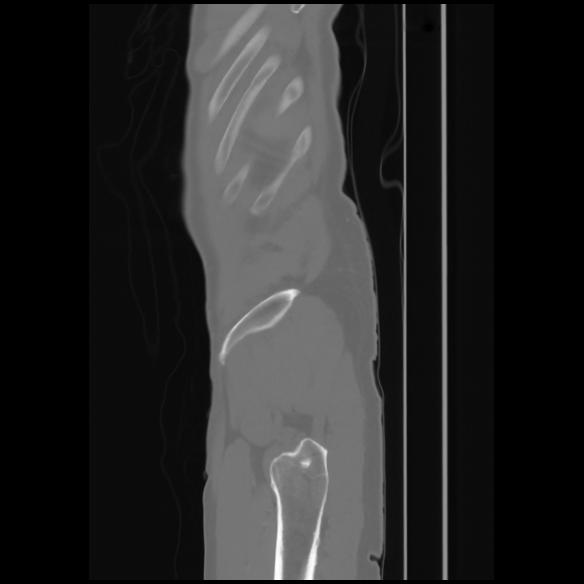

7 CUERPO,CE,Sagittal,3.000,CUERPO,Sagittal,